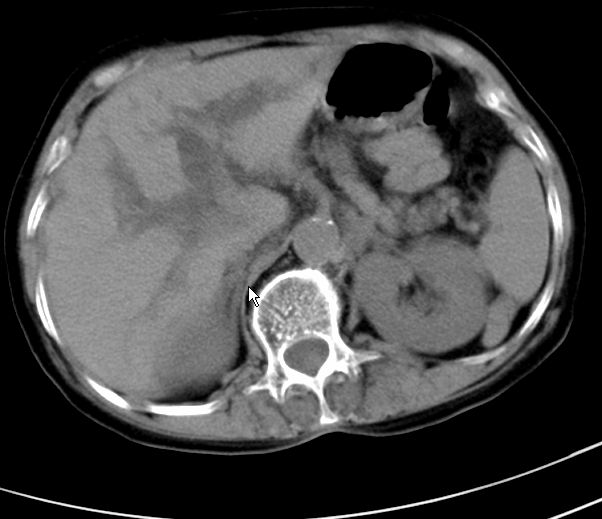

以下是引用zjzjr在2008-12-16 12:49:00的发言:[br]肝内外胆管全程扩张,胆囊明显增大,未见占位征像.建议mrcp.

以下是引用jiangjing在2008-12-16 13:19:00的发言:[br]肝内外胆管全程扩张,胆囊明显增大,扩张胆总管下段径较中上段小,未见胰管扩张,提示胆总管远端梗阻伴感染.建议增强及mrcp 检查

以下是引用朱亮在2008-12-16 12:54:00的发言:[br]胆总管远端应薄层扫描 胆总管逐渐变细 考虑胆系慢性炎症